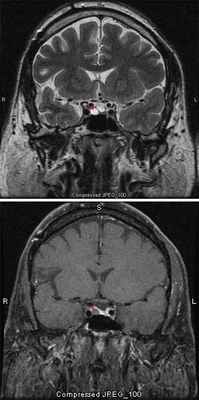

Аденомы гипофиза в настоящее время подразделяют по иммуногистохимическиой оценке секретирующих опухолью гормонов (пролактиномы, соматотропиномы и др.): Методом выбора для диагностики аденом является МРТ. Опухоли, превышающие диаметр 1 см обозначаются как макроаденомы. Сохранение функции гипофиза после обширных резекций обусловлено тем, что для поддержания гипофизарной активности требуется всего 5% массы гипофизарной ткани.

Пролактиномы составляют до трети опухолей гипофиза, являются микроаденомами, характеризуются аменореей, реже с присоединением галактореи, снижением полового влечения, умеренными головными болями. Решающим в диагностике является определение уровня пролактина в крови (норма – до 20 нг/мл) при наличии очагового увеличения гипофиза на МРТ. Небольшое увеличение пролактина (до 150 нг/мл) является неспецифичным (может быть при хронической почечной недостаточности, циррозе печении, гипотиреоидозе). Высокие показатели требуют активного, но консервативного лечения (агонист допамина – бромкриптин и др.), приводящего во многих случаях к появлению месячных, уменьшению размеров опухоли, нормализации уровня пролактина. При неэффективности консервативной терапии выполняют трансназальное удаление опухоли.

МРТ со срезами толщиной 1 мм

Вопрос об исключении опухоли гипофиза ставят при наличии головных болей, характерных расстройств зрения и эндокринопатии. Проводят нейровизуализационные исследования с толщиной среза 1 мм. МРТ более чувствительна, чем КТ, особенно для выявления микроаденом.